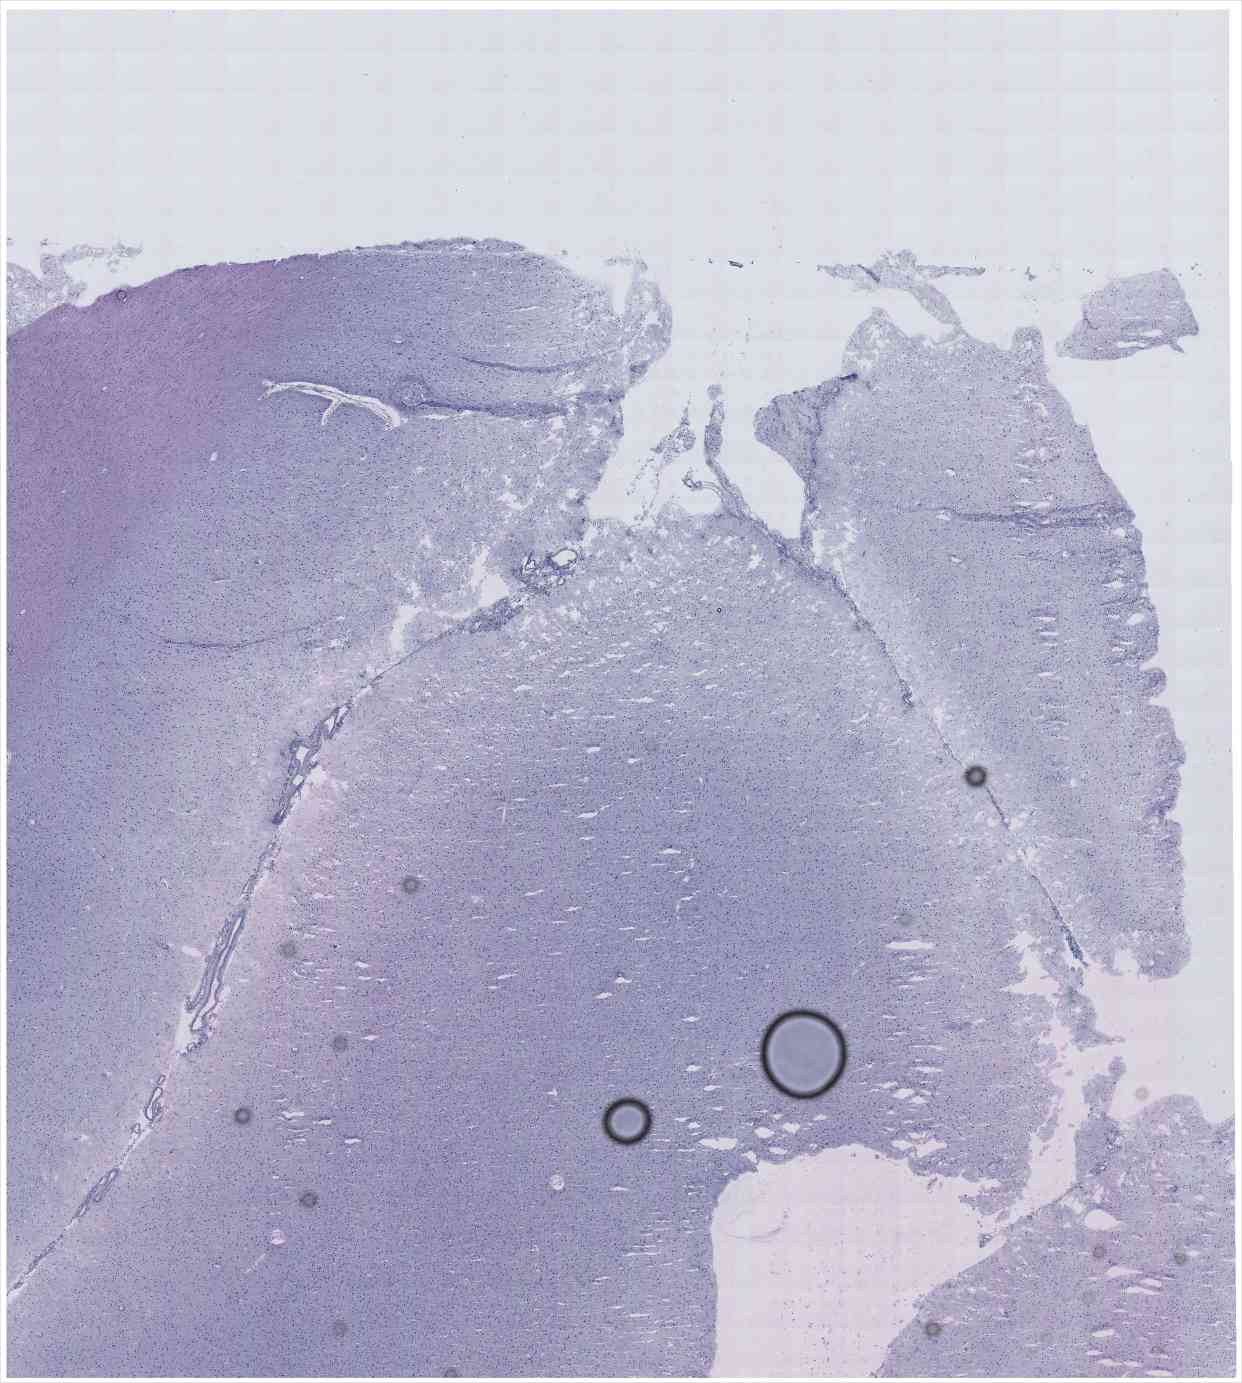

Chip 005 Well C2